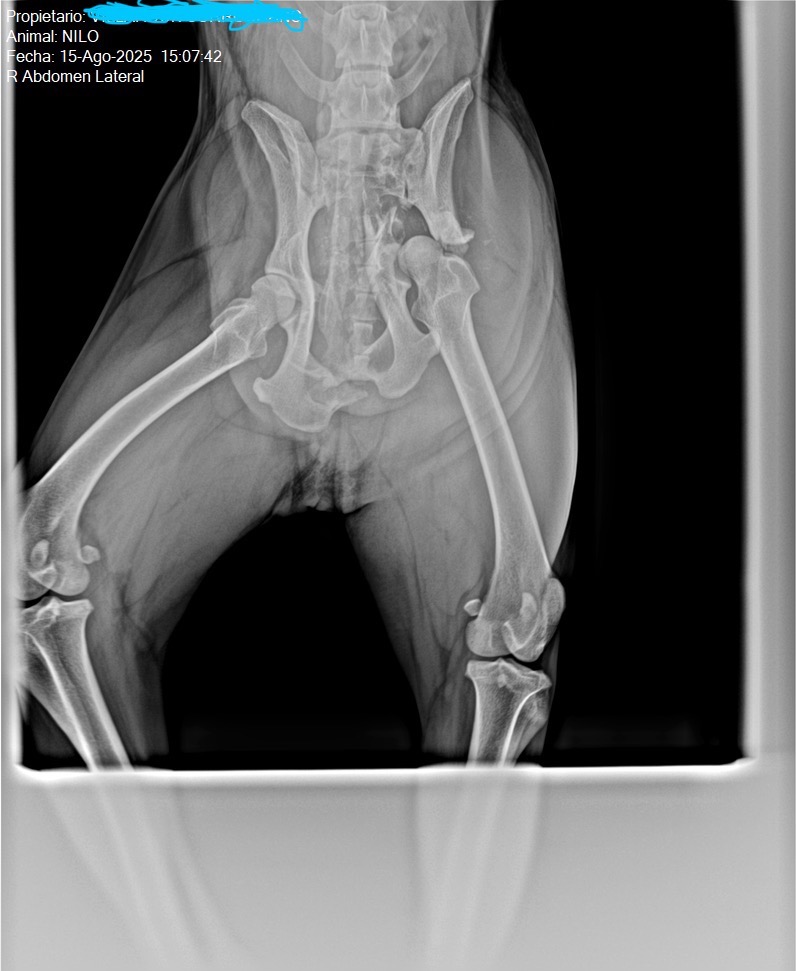

Estaba agotado, el pobre se dormía mientras le bañaba y es que ya en la bañera se caía. Pensé en un primer momento que sería de puro cansancio, pero después lo llevamos al veterinario y tras una radiografía tenía una fractura de cadera bastante acusada. El fémur partió el hueso de la cadera hundiéndose y descolocando el pubis. Adjunto imagen así como la publiqué (en redes) en su día cuando me enteré.

El veterinario valoró que había sufrido una colisión con un coche, unos pocos centímetros más arriba y lo habría matado. Tuvimos mucha suerte, dentro de todo lo malo.